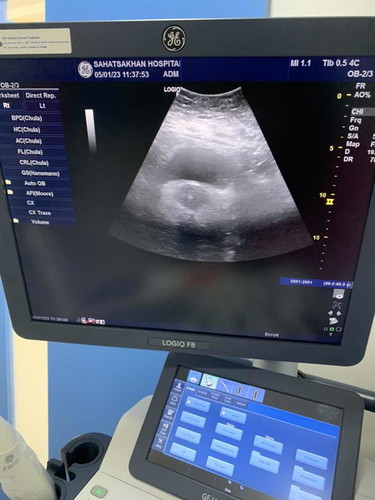

ไปฝากครรภ์พึ่งมาค่ะ บ้านนี้5W จ้า

แม่ซาว หน้าท้อง หรือช่องคลอดคะ ทำไมเห็นน้องเร็วจัง 🥰 บ้านนี้ 5+3 wk. ยังไม่กล้าไปซาวเลยค่ะกลัวยังไม่เจอน้อง